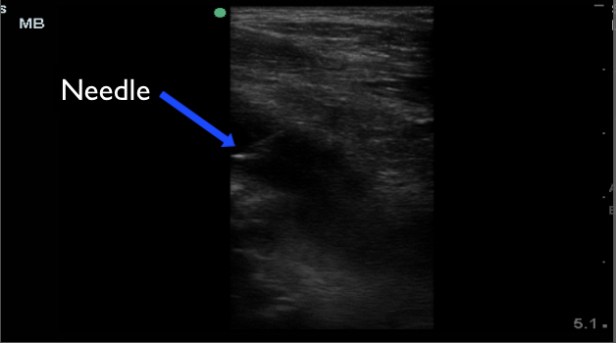

For this procedure, it is important to identify your landmarks and then take note of nearby blood vessels and nerves. I mark the location of the vessels so I am sure to avoid them during the procedure. We used an anterior approach, because the fluid collection was most accessible from this view. Using the high frequency probe, sterile technique, follow a large gauge (18) spinal needle in-plane (longitudinally) and aspirate fluid. In this case, we used procedural sedation.

The procedure was completed without issue, but we were unable to aspirate any fluid. The reason is unknown, but likely due to the chronic nature of the infection and the now near solid consistency of the collection.